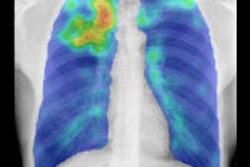

Even though Canada requires all new immigrants to undergo chest x-rays to screen for active tuberculosis, the researchers found that 87.3% of active cases came from just six countries: Afghanistan, China, India, Pakistan, the Philippines, and Vietnam. The x-rays didn't show a single case of active TB in immigrants from 179 other countries.